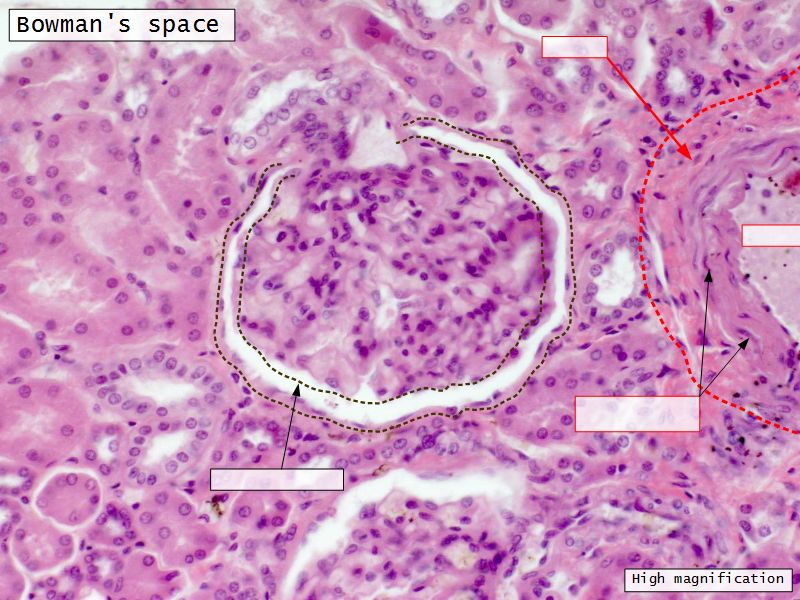

Renal corpuscle

- Tuft of capillaries

- grow into

- Blind end of nephron

- Several layers of epithelium

- Two sides

- Vascular pole

- Tubular pole

Epithelium layers

- Capillary endothelium

- Visceral layer of epithelium

- Podocytes

- Resting on glomerular basement membrane

- Capsular space

- Parietal layer of epithelium

- Simple squamous epithelium

Glomerular filtration barrier

- Three layers

- Fenestrated epithelium

- Exclude blood cells & platelets

- Glomerular basement membrane

- Main filtration barrier

- Thick

- Fused epithelial & endothelial BM

- Replenished by podocytes due to removal by mesangial cells

- Glomerular epithelium

- Through filtration slit

Podocytes

- Visceral layer of epithelium

- Protrude into capsular space

- Attached to basement membrane

- Long cytoplasmic extensions

- Primary processes

- Secondary processes

- Podocyte feet

- Tightly spaced

- Filtration slits 20 - 30 nm wide